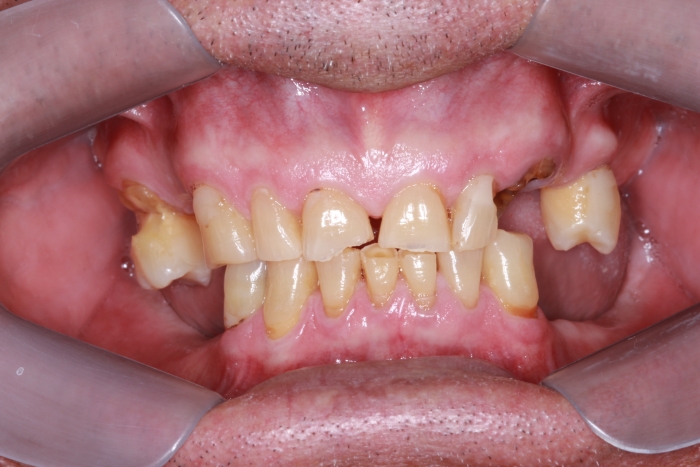

Inicial Frontal

Sorriso Inicial